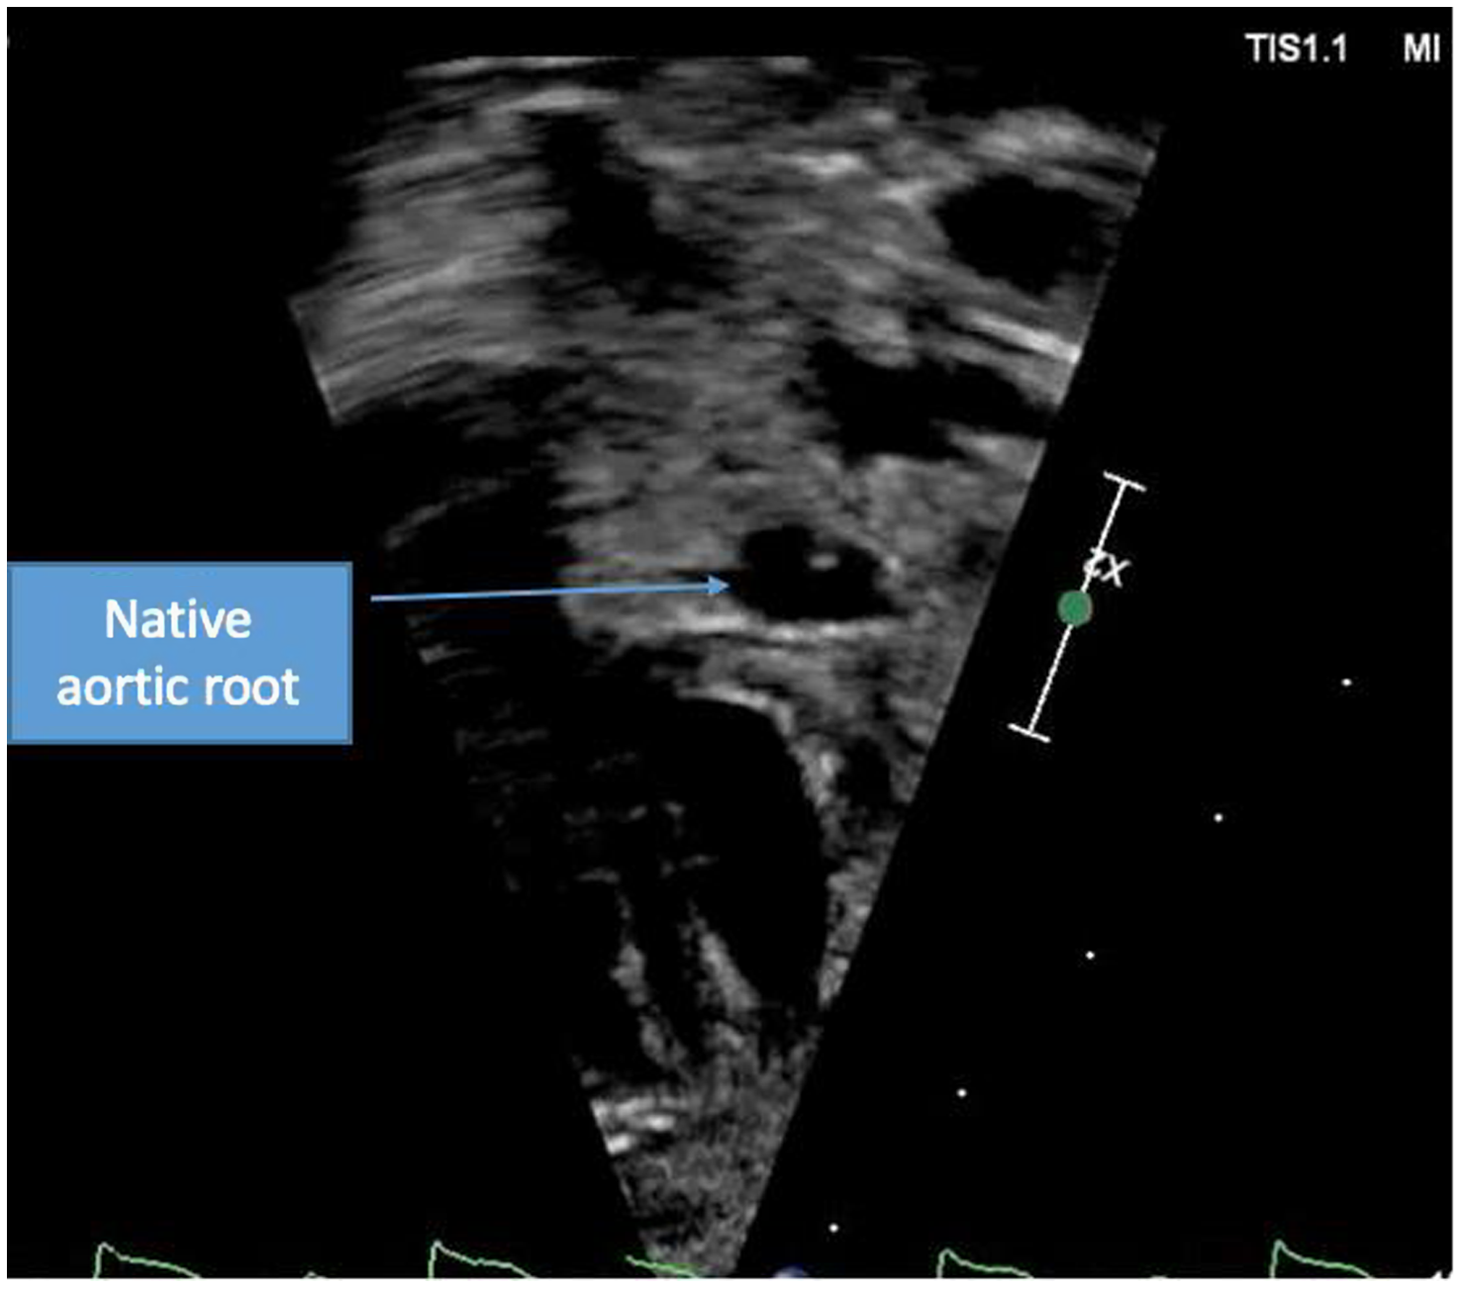

A term male infant was diagnosed postnatally at day 2 after being noted to have tachypnoea which prompted a cardiology workup and was noted to have hypoplastic left heart syndrome with severe mitral and aortic valve stenosis. At 1 week, he underwent Norwood procedure with Sano shunt placement. The Norwood was done with incising down the ascending aorta with side-to-side anastomosis with continuous monofilament sutures with knots on the outside. He had uncomplicated post-operative course and was extubated on post-operative day #5. His initial post-op echo showed unrestrictive atrial septal defect, mild tricuspid regurgitation, patent aortic arch, and Sano shunt with patent Damus–Kaye–Stansel anastomosis with no thrombus noted (Fig 1). On post-operative day #9, he was noted to have sudden onset clinical change after a routine chest physiotherapy and was noted to have sudden onset of bradycardia and hypotension, elevated ST segments with low cerebral and somatic Near Infra-Red Spectroscopy, and elevated blood lactate. A 15 Lead electrocardiogram showed ST elevation (Fig 2). His native aortic root measured around 5 mm and the ascending aorta was 4 mm. The sinotubular junction of the native aortic root measured around 4 mm. An echocardiogram showed a large thrombus (around 5 × 3.5 mm) in his aortic root occluding blood flow into the left main coronary artery (Fig 3a). His labs showed elevated troponins with an initial value of around 14 ng/ml (reference range 0–0.39 ng/ml) which peaked to around 83 ng/ml within 24 hours, with resolution over a week. The patient was intubated, started on low dose epinephrine, and sedated and paralyzed with improved haemodynamics. Haematology was consulted and the patient was started on low dose tissue plasminogen activator at around 0.06 mg/kg/hour, which was titrated to around 0.08 mg/kg/hour based on clot size. Repeat echocardiogram imaging over the next few days revealed decreasing clot size and eventual resolution of thrombus with adequate perfusion of coronary arteries after 72 hours of thrombolysis treatment (Fig 3b).

Figure 3. Short axis view of aortic root with resolution of thrombus.